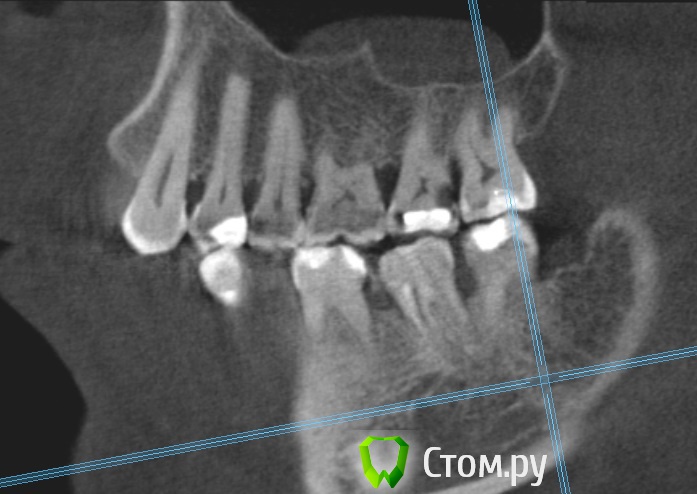

Dmitrich Опубликовано 30 сентября, 2014 Поделиться Опубликовано 30 сентября, 2014 Здравствуйте уважаемые форумчане. Вообщем такая у меня проблема, постараюсь описать менее сумбурно. Сначала я удалил 4.7 зуб из за кариеса корня. После этого примерно через неделю начались боли с другой стороны челюсти. Пришел на прием - мне по рентгену опредилили больной 3.7 (там был глубокий кариес и раза 3 переставляли пломбу на протяжении лет так 20) Его депульпировали, но боль не прошла. Сначала болело при накусывании (это нормально как я понимаю), потом просто стали ноющие боли. На месяц я уехал из города и боли были разной интенсивности. Обращался к двум разным стоматологам в отъезде - все гвоорили что это отстаточное явление после лечения. Постукивание по зубу чувствительно до сих пор. С тех пор уже 3 месяца - ноющие боли не проходят. Обращался в разные клиники, делал КТ месяц назад. Может не болеть дня 3-4 совсем, я уже обрадуюсь, на следующий день опять начинает тянуть. Утром всегда не болит, к обеду начинает. Чистили карман между 6 и 7. Результат улучшается на день-два. Ходил на прием к ортодонту, тот сказал нужно лечить 6й, состояние десен почти в норме, ко крайней мере острого воспаления нет. С КТ сделал скриншоты 6го и 7го, прикладываю. 6й зуб проверяли проводимость нерва аппаратом - результат ок )) Что мне все таки делать в данной ситуации? В клинике где лечил зуб говорят он вылечен нормально. Ссылка на комментарий

M@estro Опубликовано 30 сентября, 2014 Поделиться Опубликовано 30 сентября, 2014 Проблема в 3.6 Ссылка на комментарий

Korel Опубликовано 30 сентября, 2014 Поделиться Опубликовано 30 сентября, 2014 Проблема в 3.6 И (или) в 35 Ссылка на комментарий

Паращук Роман Опубликовано 30 сентября, 2014 Поделиться Опубликовано 30 сентября, 2014 (изменено) Или 3.6,2.7. Возможна трещина в 3.7 Изменено 30 сентября, 2014 пользователем Паращук Роман Ссылка на комментарий

Dmitrich Опубликовано 30 сентября, 2014 Автор Поделиться Опубликовано 30 сентября, 2014 Спасибо всем за советы. 2.7 сделал с месяц назад, не помогло. 3.6 получается делать точно? Странно вроде относительно недавно (года 2 назад) менял там пломбу из за того, что откололся край - вообще никаких проблем не было. Нерв проверяли - жив. То что на верхушках корня там - три месяца назад было тоже самое. А вот с трещиной вы напугали. Смотрели эту КТ несколько раз несколько стоматологов, трещину никто не увидел. Она же вроде сильно должна болеть? Ссылка на комментарий